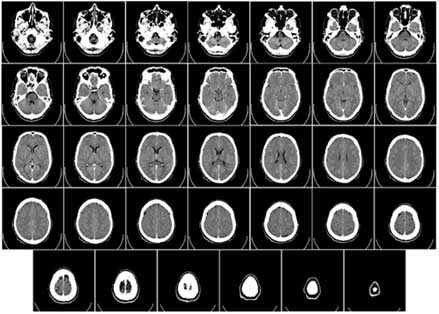

Imagen por TC mostrando estructuras internas del cuerpo

En una imagen por TC, las estructuras sobrepuestas son eliminadas, haciendo que la anatomía interna sea más aparente.

Durante la toma de imágenes por TC, un tubo de rayos X rota alrededor del paciente para que se puedan tomar múltiples imágenes desde varios ángulos. Estas imágenes se archivan en una computadora que las analiza para crear una imagen nueva en la que se han eliminado las estructuras sobrepuestas.

Las imágenes por TC le permiten a los radiólogos y a otros tipos de médicos identificar las estructuras internas y ver su forma, tamaño, densidad y textura. Esta información detallada puede ser utilizada para determinar si existe un problema médico, para evaluar la extensión y ubicación exacta del problema, y para revelar otros detalles importantes que pueden ayudar al médico determinar el mejor tratamiento. Estas imágenes también pueden determinar la ausencia de una anormalidad.